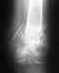

это рентгенограмма через 3 месяца после операции